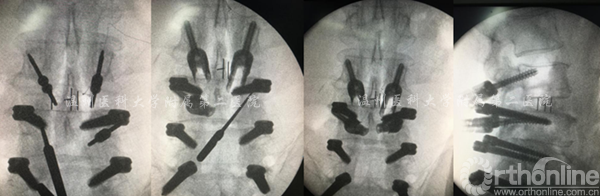

案例3

腰4-骶1行Dynesys术后3年,腰3.4椎管狭窄。

术前X线资料

术中显露置钉的过程

术中透视资料